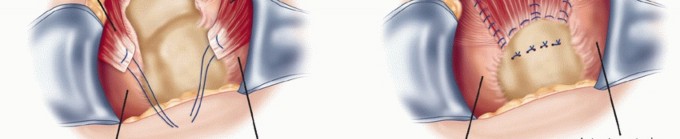

TECH FIG 4 • A. Intraoperative photograph showing freshened edges of tear. Healthy tendon is seen but not bleeding edges. Note cancellous trough at the anatomic neck and the greater tuberosity. B. Triangular tear with apex medially. C. Drawing of sutures passed through bone tunnels in the trough and greater tuberosity, pulling the edge of the cuff into the trough. Anchors can be used instead. D. Completed L-shaped repair. (D: From Neviaser R, Neviaser AS. Open repair of massive rotator cuff tears: tissue mobilization techniques. In: Zuckerman J, ed. Advanced Reconstruction: Shoulder. Chicago: American Academy of Orthopaedic Surgery, 2007:177-184.)

When the leading edge of the cuff can be brought to its insertion on the greater tuberosity, a shallow trough is made in the anatomic neck at the greater tuberosity ( TECH FIG 4A ).

Drill holes are made in the trough and the lateral side of the tuberosity and connected with a punch. Locking horizontal mattress sutures or modified Mason-Allen sutures are placed in the cuff and passed through the bone tunnels created by connecting the drill holes ( TECH FIG 4C ). Suture anchors can also be used in the trough and the tuberosity in a double-row fashion instead of the bone tunnels.

With the arm in some internal rotation and slight abduction, the sutures are tied securely to bring the free edge of the cuff into the trough.

This leaves a longitudinal split, which is sutured side to side, not only closing the split but also helping to relieve tension on the cuff advanced into the trough ( TECH FIG 4D ). -